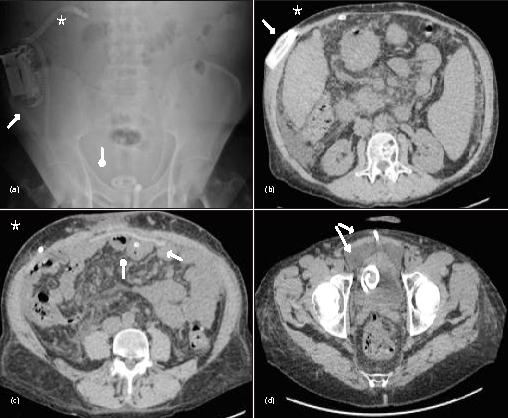

A 54-year-old man (BMI 24.2) had alcoholic cirrhosis Child-Pugh B7 since 2006. Large esophageal varices developed in 2008, treated with propanolol. In 2009, moderate ascites was treated with diuretics, complicated by spontaneous bacterial peritonitis. In 2013, he had bowel obstruction, related to strangulation of an umbilical hernia with massive ascites. The patient was hospitalized in the intensive care unit for treatment of renal failure with vasoactive amines and fluid replacement; subsequent surgical repair of the hernia by omphalectomy and placement of a peritoneal drain was performed. That drain was removed on day 13 and the patient was discharged on day 19. From 2013 to 2015, the ascites became refractory to high doses of diuretics (furosemide 80 mg a day, spironolactone 150 mg a day), required repeat paracentesis of 7 liters every 10 days, resulting in several acute kidney injury, and finaly a recurrence of the umbilical hernia. A transjugular intrahepatic portosystemic shunt (TIPS) had been considered, but was contraindicated, due to pulmonary arterial hypertension. On June 2015, a decision was made to combine implantation of a rechargeable alfapump in the abdominal wall to automatically transport the refractory ascites to the bladder. Surgical repair of the umbilical hernia was performed by placement of an intraperitoneal mesh without a peritoneal drain, during the same operation (Figure 1). Diuretics were discontinued. The alfapump was immediately activated, and the patient was out of bed on day 2, and after education on self-management of the alfapump, he was discharged on day 5. The alfapump daily target flow was gradually increased.

After 20 months follow up, the pump transported 520 liters of ascites (average of 0.951 liter per day) (Table 1, Figure 2). Hepatic function improved with a decrease in the MELD score, partly due to better renal function. With respect to quality of life, the patient had resumed physical activity the week after discharge with a daily 12-kilometer walk. The EQ-5D utility index and health state scores improved. The muscle circumferences of the triceps and quadriceps gradually increased. There was no acute kidney injury, infectious episodes, pump dislocation, poor urinary tolerance, and no recurrence of hernia. There were six periods of alfapump malfunction, at days 109 to 120, days 145 to 154, days 205 to 213, days 227 to 243, days 259 to 276, and days 370 to 380 relating to obstruction of the peritoneal catheter by the omentum, represented 12.9% of the total time. The first, third and fourth episodes was self-limiting. During the second episode, the catheter and pump were exchanged on day 154, due to obstruction by the omentum. During fifth episode, the peritoneal catheter was exchanged, due to omentum obstruction. Again, pump was exchanged during the sixth episode due to obstruction by omemtum (Figure 1). Three paracentesis were performed during follow up, at second, fifth and sixth periods of malfunction. At the time of the writing of this case report, the patient was doing well after 20 months.

A 62-year-old man (BMI 27.4) had Child-Pugh B (8) alcoholic cirrhosis, since 2008. There were no esophageal varices. He had moderate ascites, treated with diuretics and salt-free diet. In 2013, the ascites became refractory requiring repeat paracentesis of 9 liters every three weeks. The diuretics were lowered due to hypotension. The patient developed a painful umbilical hernia measuring 4 cm with skin ulceration. In the same operation, an alfapump was implanted and the umbilical hernia was repaired with omphalectomy and placement of a bioprosthesis, without peritoneal drain. The patient was out of bed on day 2. Diuretics were discontinued. The patient received education for self-management of the pump and then left the hospital on day 5. The alfapump daily target flow was gradually increase.

In 20 months follow up, the pump transported 435 liters of ascites (average of 0.775 liters per day) (Table 1, Figure 3). No paracentesis and no infusion of albumin were performed, and no ascites was detectable on ultrasound. The MELD score and renal function were stable, without infectious episodes, pump dislocation, poor urinary tolerance, or recurrence of hernia. Regarding quality of life, the utility index and health state scores improved. The muscle circumferences gradually increased. Pump malfunction occured between day 21 to day 34 (2.3% of the total time), possibly related to obstruction by the omentum. This only one single episode was self-limiting. This patient hadn’t need pump or catheter exchange during all follow up. At the time of the writing of this case report, the patient was doing well after 20 months.